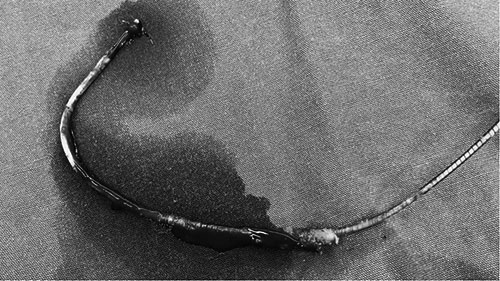

拔除体外的电极导线。电极表面可见疤痕组织和血栓